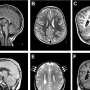

Why do some children develop a brain that is too small (microcephaly)? An international research team involving the German Primate Center—Leibniz Institute for Primate Research (DPZ), Hannover Medical School (MHH), and the Max Planck Institute of Molecular Cell Biology and Genetics has used human brain organoids to investigate how changes in important structural proteins in the cell lead to this severe developmental disorder.